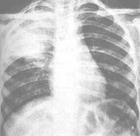

2.肺部X光檢查:呈現大葉性肺炎(單一肺葉出現變化)。

2.肺部X光檢查:肺部呈現瀰漫性或浸潤性的肺炎,且可能五片肺葉皆多有少變化。